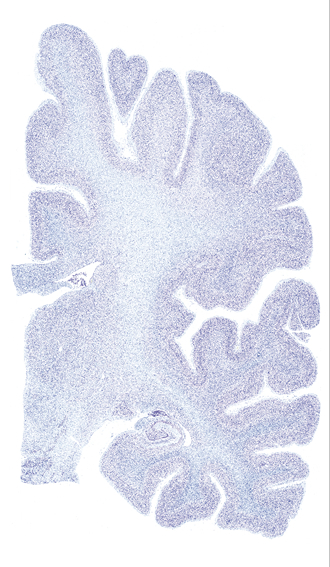

Hi-Resolution Sections · Cells (Nissl Staining) · Virtual Microscopy

Frontal sections (Nissl) from the Atlas Brain:

Slice ID:

r3-0501

Plate NR:

40

Position:

23,9 mm